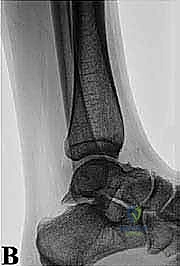

* الأشعة السينية (X-rays): بوضعيات خاصة (Lateral view) لرؤية العظم الزائد (Os Trigonum) والنتوءات العظمية وتضيق المسافات المفصلية.

* التصوير بالرنين المغناطيسي (MRI): هو المعيار الذهبي. يكشف بدقة متناهية عن التهابات الأوتار (مثل FHL)، ارتشاح السوائل، تمزقات الأربطة، ووذمة نخاع العظم (Bone Marrow Edema) التي لا تظهر في الأشعة العادية.

* الأشعة المقطعية (CT Scan): تُستخدم في حالات معينة لعمل خريطة ثلاثية الأبعاد للكسور القديمة أو التكلسات العظمية المعقدة قبل الجراحة.